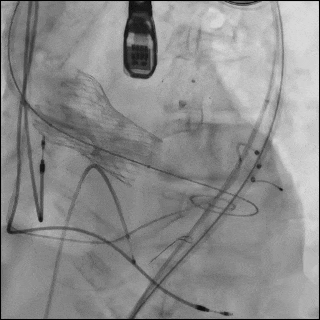

图6 逐步操作过程

(A)使用 21 mm TRUE balloon 行主动脉瓣预扩张。于钙化的 Evolut R valve 瓣叶水平可见明显“球囊腰征”(白色箭头),提示充盈过程中存在显著阻力。(B)植入 23 mm SAPIEN 3 Ultra RESILIA valve(S3UR)过程中发生球囊破裂。球囊远端可见造影剂积聚(白色箭头),形成类似“伞状”外观,提示存在水平撕裂。23 mm 瓣膜未完全释放(白色箭头)。(C)对侧入路行髂动脉造影。可见左侧髂总动脉夹层,但无活动性造影剂外渗(白色箭头)。(D)使用 23 mm TRUE balloon 对未完全扩张的 S3UR 瓣膜进行后扩张。(E)血管内干预后髂动脉造影。将 16F eSheath 回撤至左侧髂外动脉,并于夹层的髂总动脉内植入一枚 8 × 59 mm VBX 覆膜支架(白色双向箭头)。(F)血管内干预后股动脉造影。左侧股总动脉穿刺通路采用 7 × 50 mm Viabahn stent graft 进行封闭(白色双向箭头)。最终造影显示无造影剂外渗,血流通畅。

随后植入23 mm S3UR 瓣膜,其流出端与既往瓣膜支架的 node 4.5对齐。球囊扩张过程中发生破裂,导致瓣膜未完全扩张。球囊远端内造影剂积聚提示存在水平撕裂,形成“伞状”结构,使系统无法通过14F鞘管回撤(图6B,视频7)。